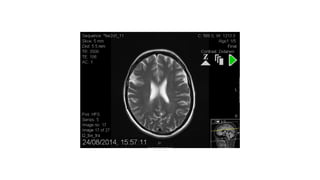

RR 20 year old male, left then right leg paraesthesia and

weakness

progressing to left upper limb and torso involvement,

commenced Oct 2014